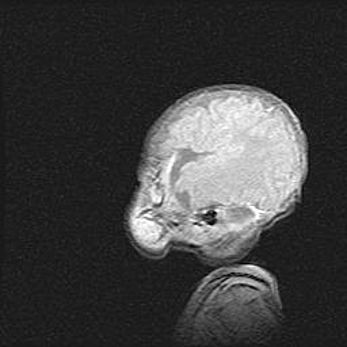

Церебральная ишемия II.

Возраст: 5 дней

Вес: 3400 г

Пол: женский

Окружность головы: 35 см

Срок гестации: 39 недель

Церебральная ишемия – это заболевание, характеризующееся недостаточностью (гипоксией) либо полным прекращением (аноксией) снабжения мозга кислородом по причине закупорки одного или нескольких сосудов. Это приводит к  что метаболическим расстройствам различной степени тяжести в тканях головного мозга, развитию коагуляционных некрозов и гибели нейронов.